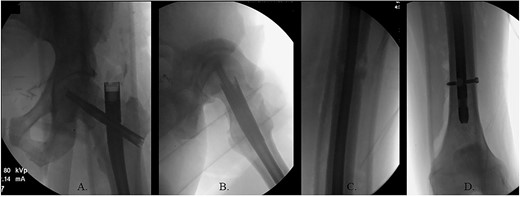

The hip was extended, and a ball-tipped guidewire was successfully passed across the fracture site to a center–center positionwithin the canal at the level of the knee (Fig. 4C and D). Sequential 0.5-mm reaming from 9 to 13 mm prepared for an 11 × 400 mm, 125° Gamma3® intertrochanteric rod (Stryker© Kalamazoo, MI), with a 95-mm cephalomedullary screw and ×2 distal lateral to medial interlocking 5.0-mm screws (Fig. 5A–D). Through the course of the procedure, 400 cc of blood loss necessitated two units of packed red blood cells.

The patient immediately was weight-bearing as tolerated to the operative extremity and worked with physical therapy (PT) to include 80 ft on post-operative day (POD) #2 with use of a front-wheeled walker. He continued to progress with PT and was discharged home POD #8 with home health/PT. At 12 months, the patient denied pain, and XRs demonstrated robust callus formation and bridging healing at the fracture site (Fig. 6).

(A) 12-month post-operative AP radiograph of left hip; (B) 12-month post-operative lateral radiograph of left hip; (C) 12-month post-operative lateral femur radiograph; (D) 12-month post-operative AP distal femur radiograph.